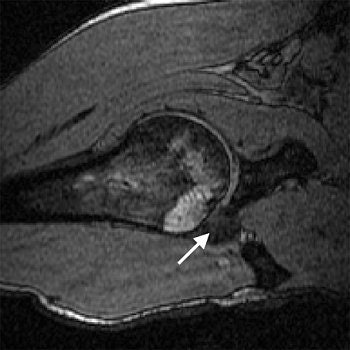

| Transverse 3D gradient-echo MR images (30/10) with volunteer in neutral position (above), unloaded ABER position at 90° external rotation (middle), and 111° external rotation (below). Note infraspinatus tendon (arrow) deformed between the greater tuberosity and posterosuperior glenoid in the loaded study. |

Based on the image evaluation, contact was observed between the supraspinatus and the posterosuperior glenoid in the unloaded and loaded ABER positions in all eight volunteers. Again, in all eight subjects, contact was noted between the infraspinatus near the insertion and posterior glenoid in the loaded and unloaded positions. Four cases were deemed grade 2. Intraobserver agreement between the two radiologists on supraspinatus and infraspinatus tendon contact with the glenoid was excellent (k = 0.875).

The researchers also assessed minimum distances and noted changes in distance in the loaded ABER position. They found that the minimum distance between the supraspinatus insertion and the acromion dipped from 16.9 mm to 5.7 mm, while the infraspinatus to glenoid distance went from 38.4 mm to 3.6 mm. The supraspinatus to glenoid distance went from 35 mm to 6.6 mm. Finally, the distance between the greater tuberosity and glenoid decreased from 21.5 mm to 3.6 mm.

This last result suggested that "a larger portion of the greater tuberosity (including the supraspinatus and infraspinatus insertions) may be important in the minimum distance measurement," the authors stated. "The infraspinatus insertion, in particular, came to within 3.6 mm from the glenoid, on average."